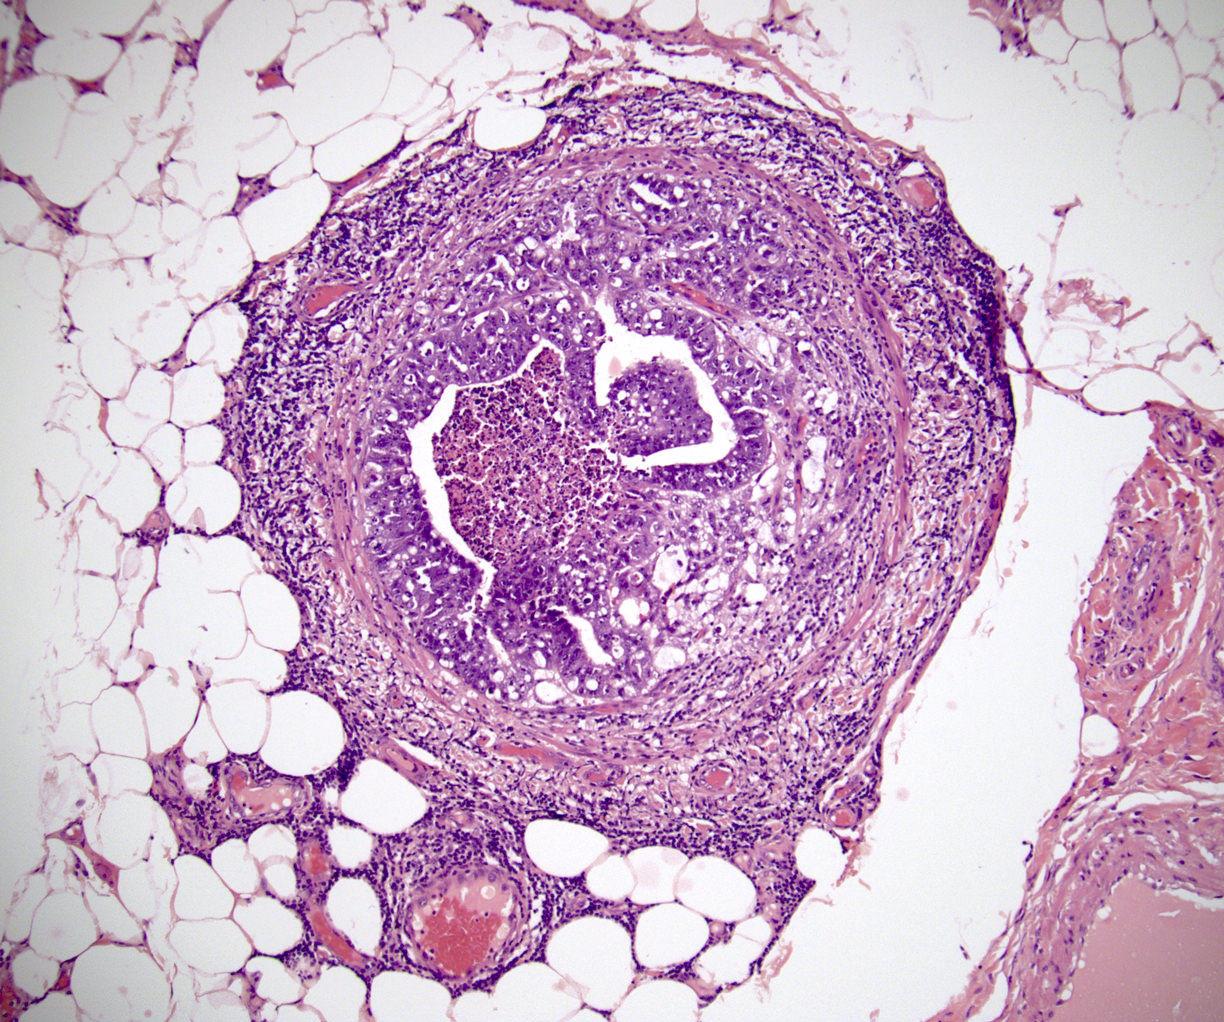

Microscopic (histologic) images

Board review style question #1

In a postpubertal testicular germ cell tumor, lymphovascular (shown above), hilar fat, epididymal and tunica vaginalis invasion are all a part of which pT category?

Board review style answer #1

D. pT2. Lymphovascular, hilar fat, epididymal and tunica vaginalis invasion are all a part of the pT2 category for testicular germ cell tumors. Lymphovascular invasion by embryonal carcinoma is shown in the image.

Comment Here Reference: